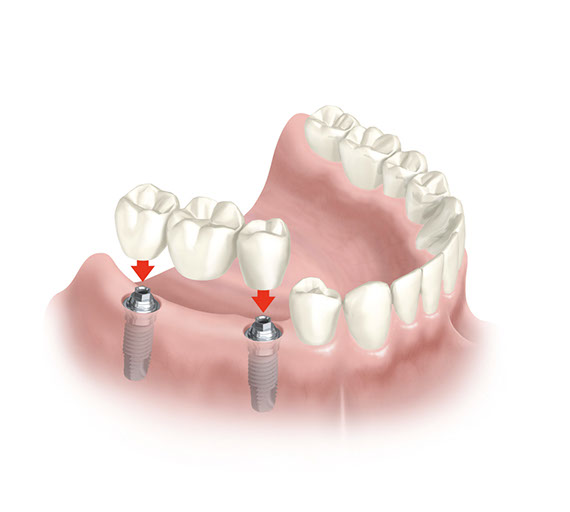

L’assemblaggio tra Impianto e Protesi

Tolta definitivamente la Vite di Guarigione si avvitano i Pilastri, ciascuno per ogni Impianto.

Ogni Pilastro farà da sostegno alla Protesi.